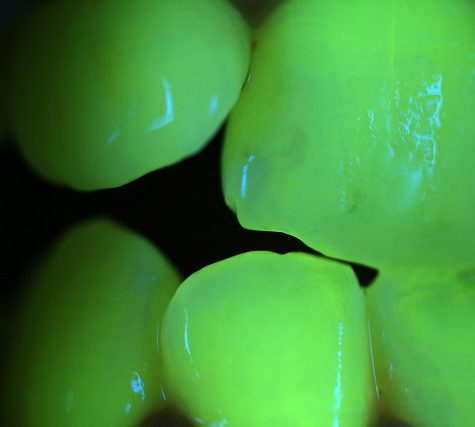

A tooth (plural teeth) is a hard, calcified structure found in the jaws (or mouths) of many vertebrates and used to break down food. Some animals, particularly carnivores, also use teeth for hunting or for defensive purposes. The roots of teeth are covered by gums. Teeth are not made of bone, but rather of multiple tissues of varying density and hardness. The cellular tissues that ultimately become teeth originate from the embryonic germ layer, the ectoderm.

A tooth (plural teeth) is a hard, calcified structure found in the jaws (or mouths) of many vertebrates and used to break down food. Some animals, particularly carnivores, also use teeth for hunting or for defensive purposes. The roots of teeth are covered by gums. Teeth are not made of bone, but rather of multiple tissues of varying density and hardness. The cellular tissues that ultimately become teeth originate from the embryonic germ layer, the ectoderm.

A tooth (plural teeth) is a hard, calcified structure found in the jaws (or mouths) of many vertebrates and used to break down food. Some animals, particularly carnivores, also use teeth for hunting or for defensive purposes. The roots of teeth are covered by gums. Teeth are not made of bone, but rather of multiple tissues of varying density and hardness. The cellular tissues that ultimately become teeth originate from the embryonic germ layer, the ectoderm.

A tooth (plural teeth) is a hard, calcified structure found in the jaws (or mouths) of many vertebrates and used to break down food. Some animals, particularly carnivores, also use teeth for hunting or for defensive purposes. The roots of teeth are covered by gums. Teeth are not made of bone, but rather of multiple tissues of varying density and hardness. The cellular tissues that ultimately become teeth originate from the embryonic germ layer, the ectoderm.

A tooth (plural teeth) is a hard, calcified structure found in the jaws (or mouths) of many vertebrates and used to break down food. Some animals, particularly carnivores, also use teeth for hunting or for defensive purposes. The roots of teeth are covered by gums. Teeth are not made of bone, but rather of multiple tissues of varying density and hardness. The cellular tissues that ultimately become teeth originate from the embryonic germ layer, the ectoderm.

A tooth (plural teeth) is a hard, calcified structure found in the jaws (or mouths) of many vertebrates and used to break down food. Some animals, particularly carnivores, also use teeth for hunting or for defensive purposes. The roots of teeth are covered by gums. Teeth are not made of bone, but rather of multiple tissues of varying density and hardness. The cellular tissues that ultimately become teeth originate from the embryonic germ layer, the ectoderm.